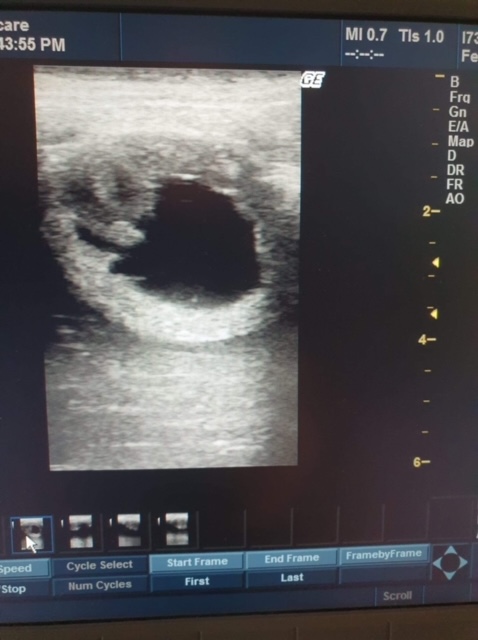

Anbefales fra 17 dager etter siste bedekking eller inseminering for å kunne avdekke tvillinger, og før behov for eventuell ny bedekning på hopper som ikke har blitt drektige (ny brunst kommer normalt innen 19-21 dager etter forrige, litt avhengig av vær og temperatur.)

Kan utføres for brunstkontroll, eller for å prøve finne årsak til at hopper ikke har blitt drektige. For å stadfeste brunst, er det som oftest nødvendig med flere undersøkelser, det kan være nødvendig å sjekke hopper annenhver dag for å peile inn brunst. Da kan reiseavstand, kostnader og tilgjengelig veterinær være avgjørende, og igjen er behandlingsrommet på travbanen å anbefale.